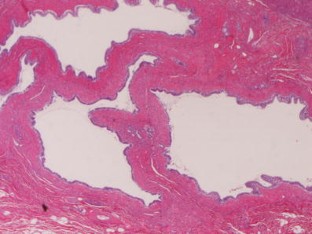

We herein report a case of monolobar hepatobiliary fibropolycystic disease. A 75-year-old woman presented with heartburn. Imaging modalities including US, CT, and MRI revealed marked atrophy and multiple biliary cysts of the hepatic left lobe. The hepatic right lobe was normal. ERCP and bile duct endoscopy revealed anomalous pancreaticobiliary union, choledochal dilation, dilation of left intrahepatic bile ducts, and small choledochal non-invasive adenocarcinoma. Polycystic kidney diseases were absent. The patient underwent pancreatico-duodenectomy and extended hepatic left lobectomy. Grossly, the hepatic left lobe was markedly atrophic, and studded with numerous biliary cysts. The left intrahepatic bile ducts were dilated (Caroli’s disease) and the common bile duct showed type I choledochal dilation. The right hepatic lobe was normal. Histologically, the hepatic left lobe was replaced by fibroelastosis. The intrahepatic bile ducts showed ductal plate malformation such as irregular contours, invaginations, and protrusions. The numerous biliary cysts also showed ductal plate malformation. There were numerous persistent ductal plates and microhamartomas. Many hyalinized destructive biliary cysts and ductal plates were recognized. The liver parenchyma was scant and free of hepatocellular malformations. The portal veins showed old obliterative portal thrombosis. The right hepatic lobe was normal. Immunohistochemically, the biliary cells were positive for cytokeratin 7, 8, 18 and 19, and MUC6 and CD10, but negative for MUC2 and MUC5AC. The biliary cysts, persistent ductal plate, and microhamartomas were positive for fetal apomucin antigen MUC1.

Fig. 3